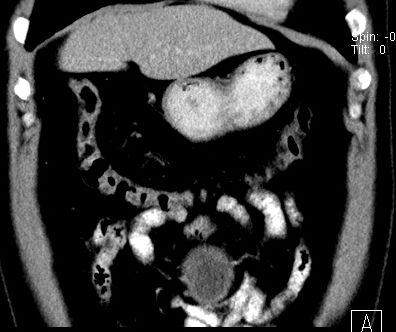

男,48岁,间断性下腹不适1年。

手术探查

:距回盲部28厘米处肠系膜根部可见5*7cm左右包块,质中等硬度,活动度尚可,肝、胆、胰、脾肾未见明显异常。

病理

:(腹腔)

神经鞘瘤

,伴出血、坏死及囊性变,伴淋巴结反应性增生。

免疫组化结果

:sma(-), desmin(-), cd117(-), s-100(+++), nf(-),vimentin(+++).